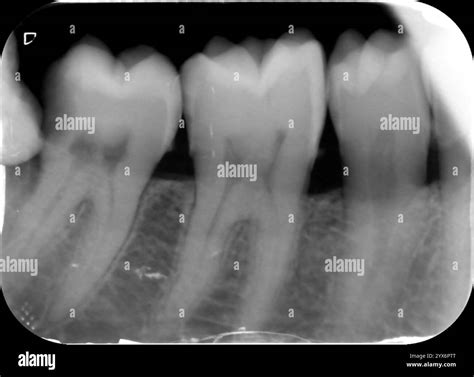

The Crown X Ray Dental technology utilizes advanced imaging techniques to capture high-resolution images of the teeth, jaws, and surrounding tissues. Unlike traditional X-rays, which provide a two-dimensional view, Crown X Ray Dental offers a three-dimensional perspective. This allows dentists to see the internal structure of the teeth and bones in greater detail, making it easier to identify issues that might not be visible with conventional methods.

Crown X Ray Dental technology is particularly useful for diagnosing conditions such as:

• Cavities and tooth decay

• Infections and abscesses

• Bone loss and gum disease

• Impacted teeth and wisdom teeth issues

• Cysts and tumors

• Fractures and cracks